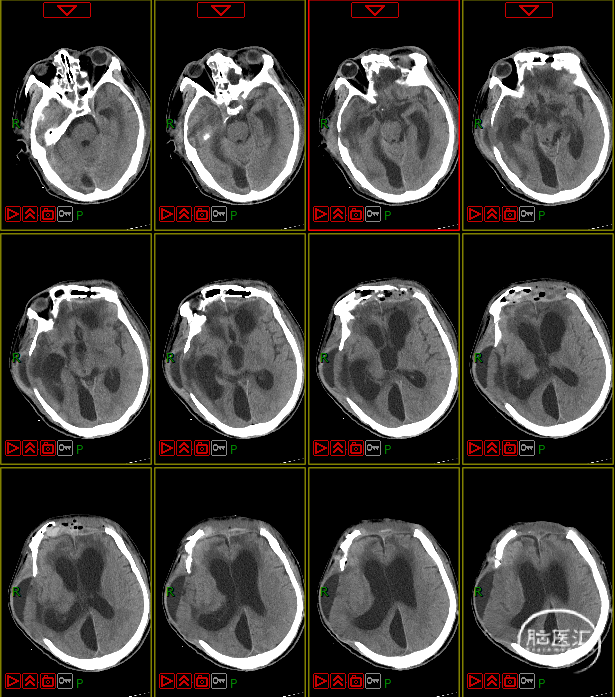

湘潭市中心医院南院骨科治疗

1. 高压氧治疗:评估有无禁忌症,于8月4日启动高压氧治疗。

2. 药物治疗:护脑、抗感染、化痰、营养支持、护肝、护胃、抗凝等治疗方案,同时动态复查血常规、肝肾功能、电解质、凝血功能,监测感染指标,定期复查痰培养。

3. 多学科会诊指导治疗:神经内科、神经外科、营养科、消化内科、高压氧舱、呼吸内科、临床药学、康复科、烧伤科、普外科会诊等。

4. 动态复查头部CT

8月21日复查CT:硬膜下积液增加,脑室扩张明显,间质性水肿加重;对患者治疗方案进行调整,转神经外科治疗。